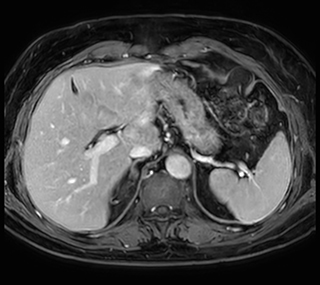

These are some images of a cardiac cine scan with a short breath-hold time. A high temporal resolution provides a smooth cine, which helps in assessing heart function. Ingenia Ambition.

Ingenia Ambition, 3D breath hold, FOV 370 mm, voxels 1.51 x 1.58 x 4.0 mm, 120 slices, scan time 19.6 sec.